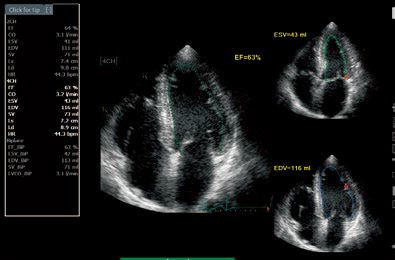

Auto EF

心内膜面を自動トレースし、駆出率(EF)や

1回拍出量(SV)を算出できます。